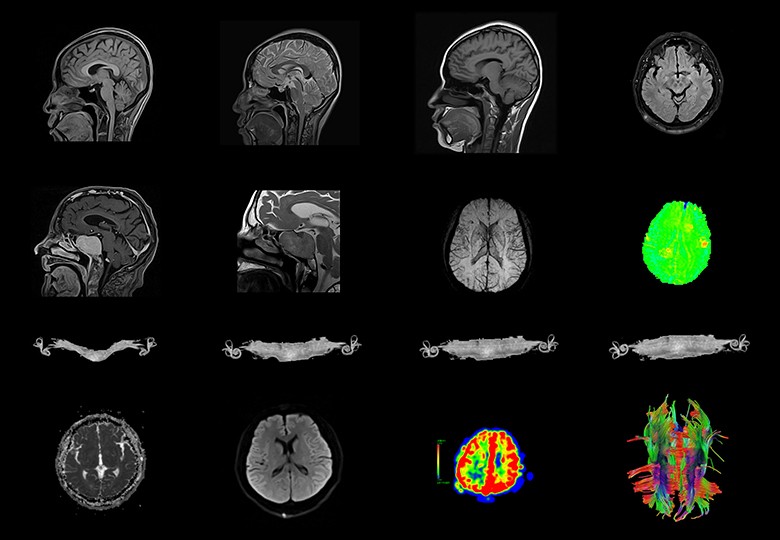

Album d'images cliniques

• Tête